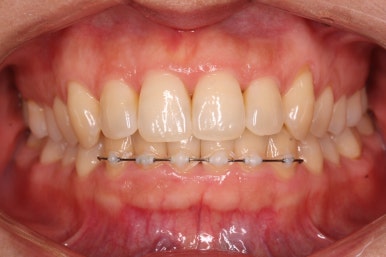

부산설측교정 키다리아저씨치과에서 부분교정을 마무리 하였습니다.

장치를 모두 제거하고 유지철사를 안쪽으로 부착하고 치료를 종료하였습니다.

전후사진을 비교해 보겠습니다.

삐뚤었던 부위들은 가지런하게 정리가 되었습니다.